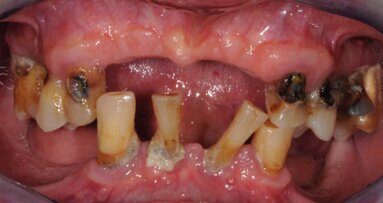

La paziente, B.G. di sesso femminile, di anni 71, è giunta alla nostra osservazione per la mobilità e lieve dolore a carico dell’elemento 2.2 (incisivo laterale superiore sinistro) (Fig. 1). All’esame ispettivo l’elemento presenta mobilità di grado 3. Al sondaggio parodontale presenta una tasca mesiale di 7 mm e di 3 mm lungo le altre superfici del dente. All’esame radiografico, eseguito con radiografia endorale periapicale, si osserva un’area di radiotrasparenza riconducibile a riassorbimento osseo soprattutto in sede mesiale (Fig. 2).

Il dente presenta un trattamento canalare e un restauro in ceramica integrale. La radice appare di dimensioni ridotte, con un supporto parodontale ridotto. La paziente è da molti anni in fase di mantenimento dopo trattamenti parodontali e la situazione è stabile da molti anni, con una buona compliance e assenza di fattori di rischio generali. Considerando le varie opzioni di trattamento, anche tenendo presenti le richieste della paziente, è stata scelta l’opzione della sostituzione del 2.2 mediante impianto osseointegrato.